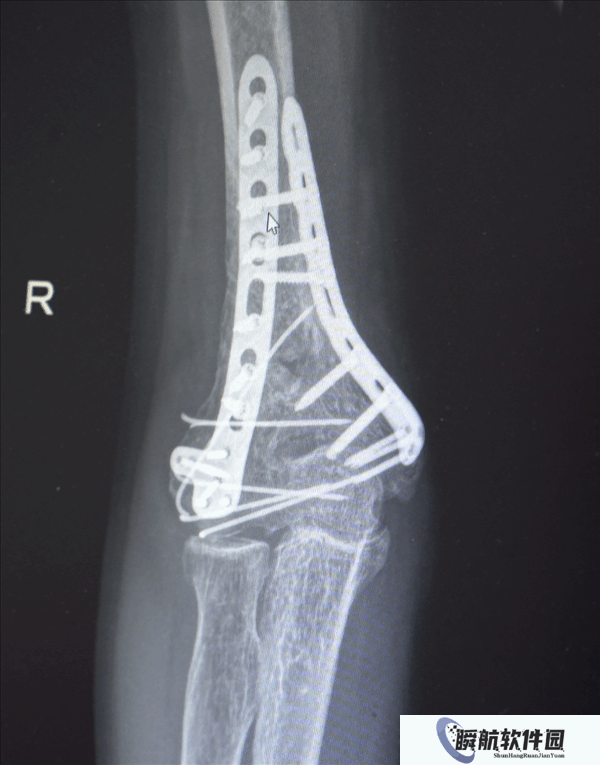

鉴于男子多处骨折,其中最严重的当属右肘部C3型粉碎性骨折,关节面及髁上严重粉碎(碎成了七块),肘关节易粘连,复位固定难度极高。

最终医疗团队采用了“拼古董”式复位固定技术,就像修复一件珍贵的古董瓷器,先拼接大块骨块再贴合小块,先后进行了两次手术。